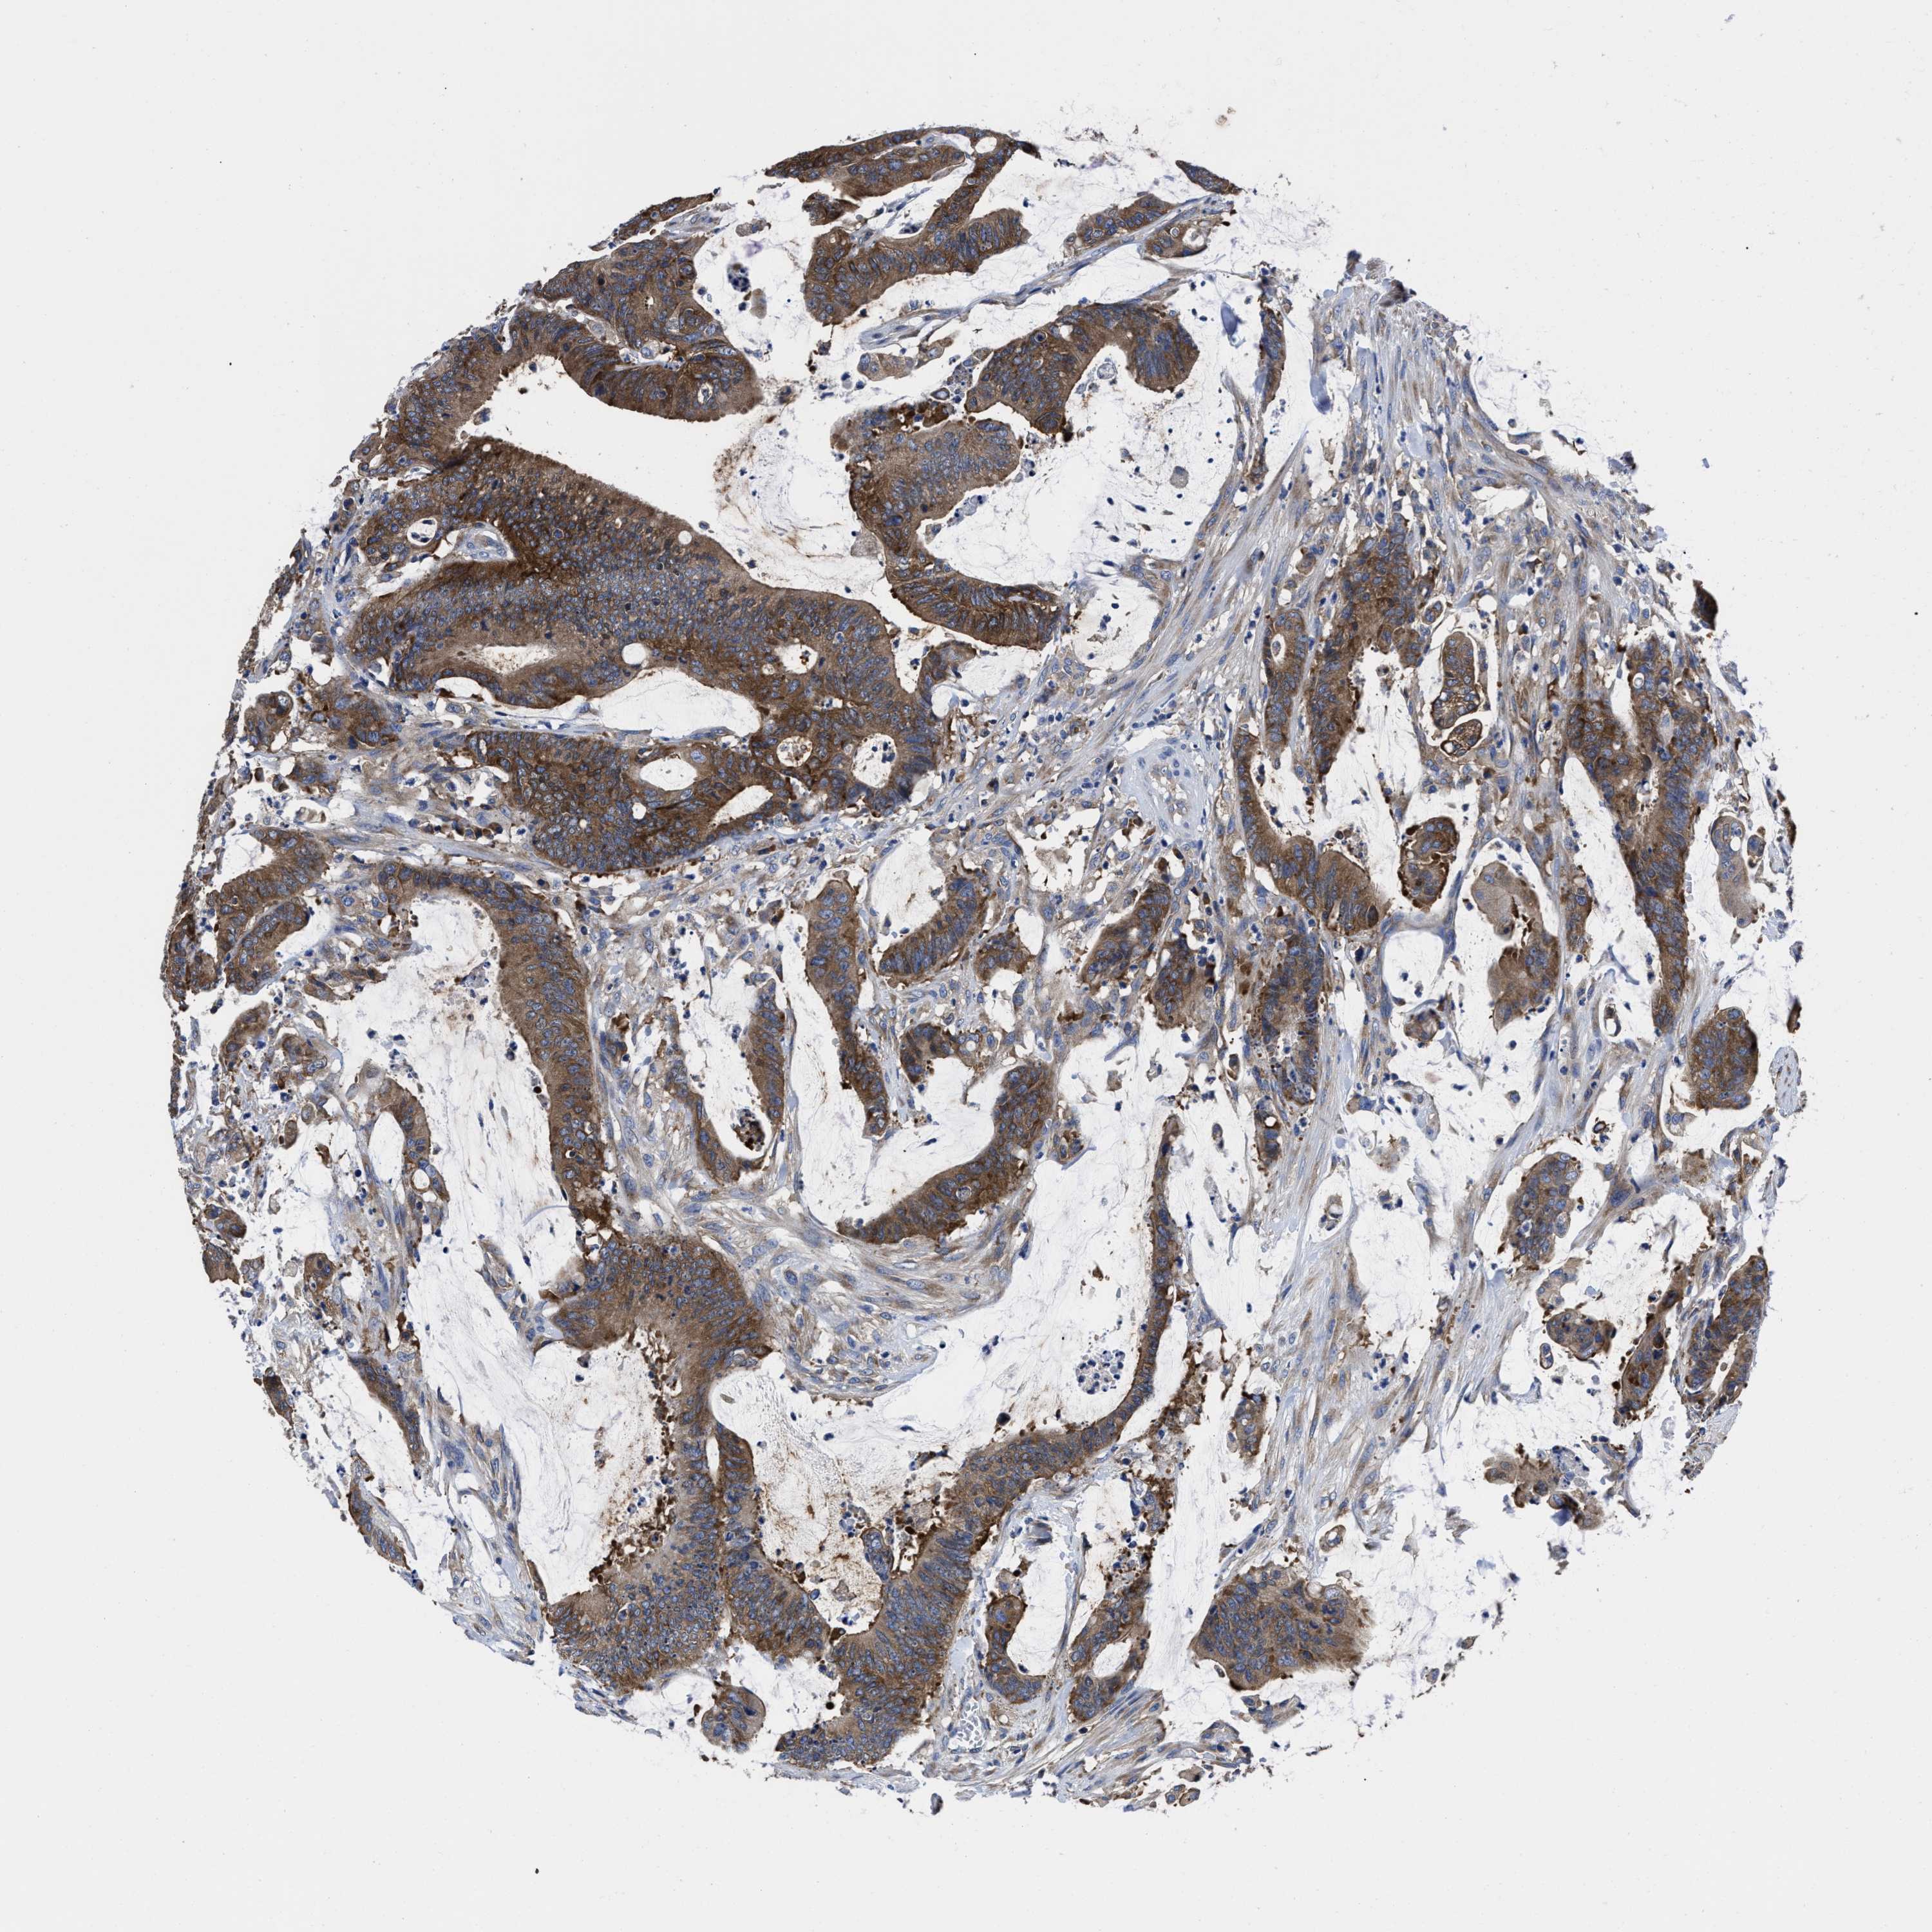

CANCER COLORECTAL CANCER Show tissue menu

Colorectal cancer

Human cancer

Colon adenocarcinoma